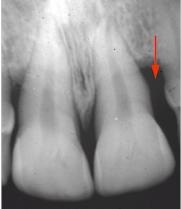

Il peut en être de même pour une poche parodontale.

Un contact glissant au cours de la fonction mandibulaire peut être à l'origine d'un abcès parodontal.